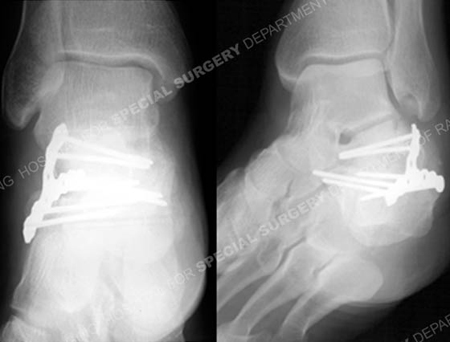

Postoperative radiographs at 6 months demonstrating a healed calcaneus fracture.